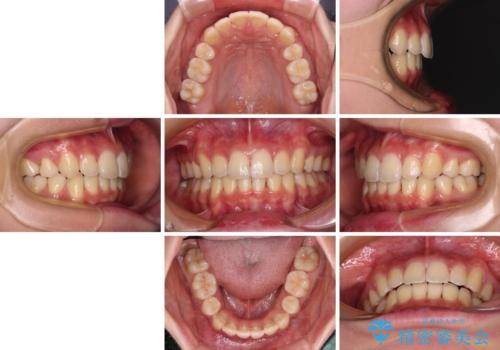

短期間で口元の突出感を改善 ワイヤー装置での抜歯矯正

- 口元の閉じにくさを気にして来院された患者様です。

上下ともに歯列が前方に突出していたため、上下左右の第一小臼歯4本を抜去し、ワイヤー装置による矯正治療を行うこととしました。

舌の突出癖による影響もあったため、舌のトレーニングを並行して実施しました。

上下左右4本抜歯する場合には、通常2年から2年半ほどの期間を要しますが、僅か1年半で終了することができました。